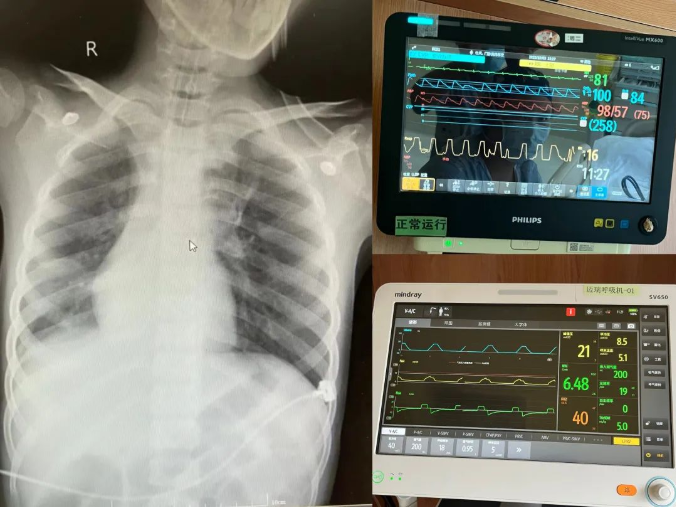

左:支气管镜术后复查床旁胸片显示病变较前明显好转,纵隔及气管较前复位

右:监护室中监护仪显示患者氧合100%,呼吸频率下16次/分,气道峰压21mmHg

患儿复查时胸片显示病变较前明显好转,纵隔及气管较前复位。根据迅速检测明确的病原学检测结果,牟向东和儿科主任徐樨巍、主任医师晁爽、主治医师尹小梅、LICU主任医师张振宇、主治医师李姗等为患者制定了下一步的治疗方案。